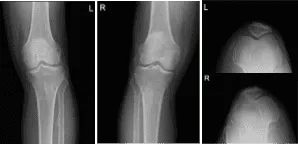

Presentó una radiografía de sus rodillas bilaterales, columna lumbar y mano derecha de Zwanger. Los resultados de sus radiografías mostraron cambios degenerativos osteoartríticos leves. No hay fracturas. Para su columna lumbar, cambios degenerativos lumbares multinivel leves. Para su mano derecha, mano derecha normal.

Radiografía de rodilla izquierda y derecha con rótula